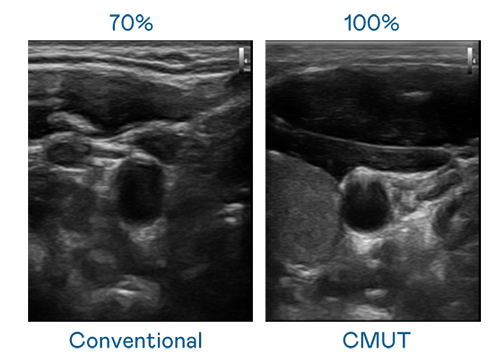

CMUT 技術是一種用電容式微機電元件來產生超音波訊號的技術。與傳統 PZT 壓電式技術相比,CMUT 頻寬增加 30%,更寬頻的超音波訊號讓影像解析度大幅提升,是實現高影像品質醫療超音波掃描、促進精準醫療發展的關鍵技術。

超音波影像的解析度高低,首先取決於探頭能發出的訊號頻寬。九游会 CMUT 可提供高清晰的超音波訊號,提供高頻寬、高靈敏度、影像紋理細節更高的超音波影像,協助醫護人員縮短影像判讀時間及利用精準的醫療影像進行診斷。